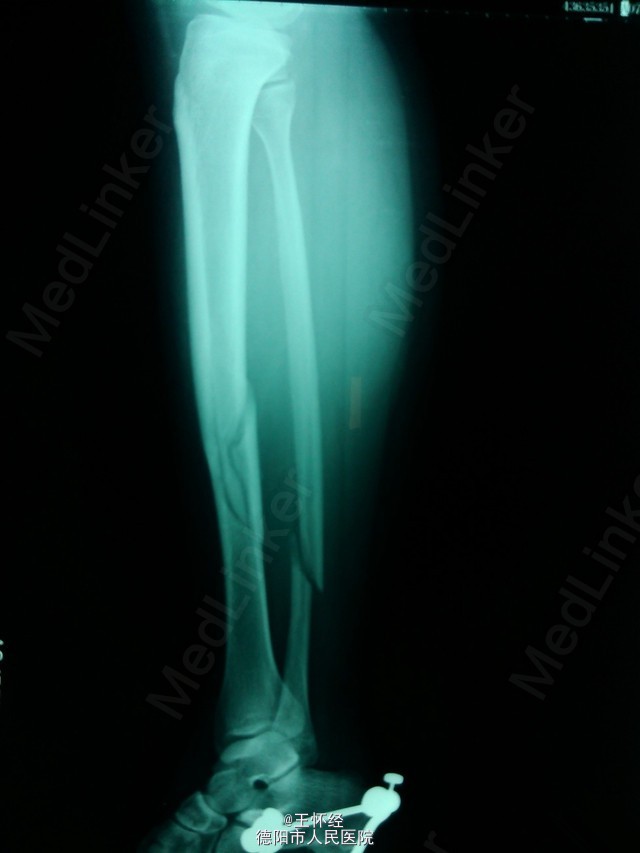

胫腓骨骨折闭合复位

患者女性,26岁,3日前滑雪致右胫腓骨粉碎性骨折,待时机适合时行手术治疗。